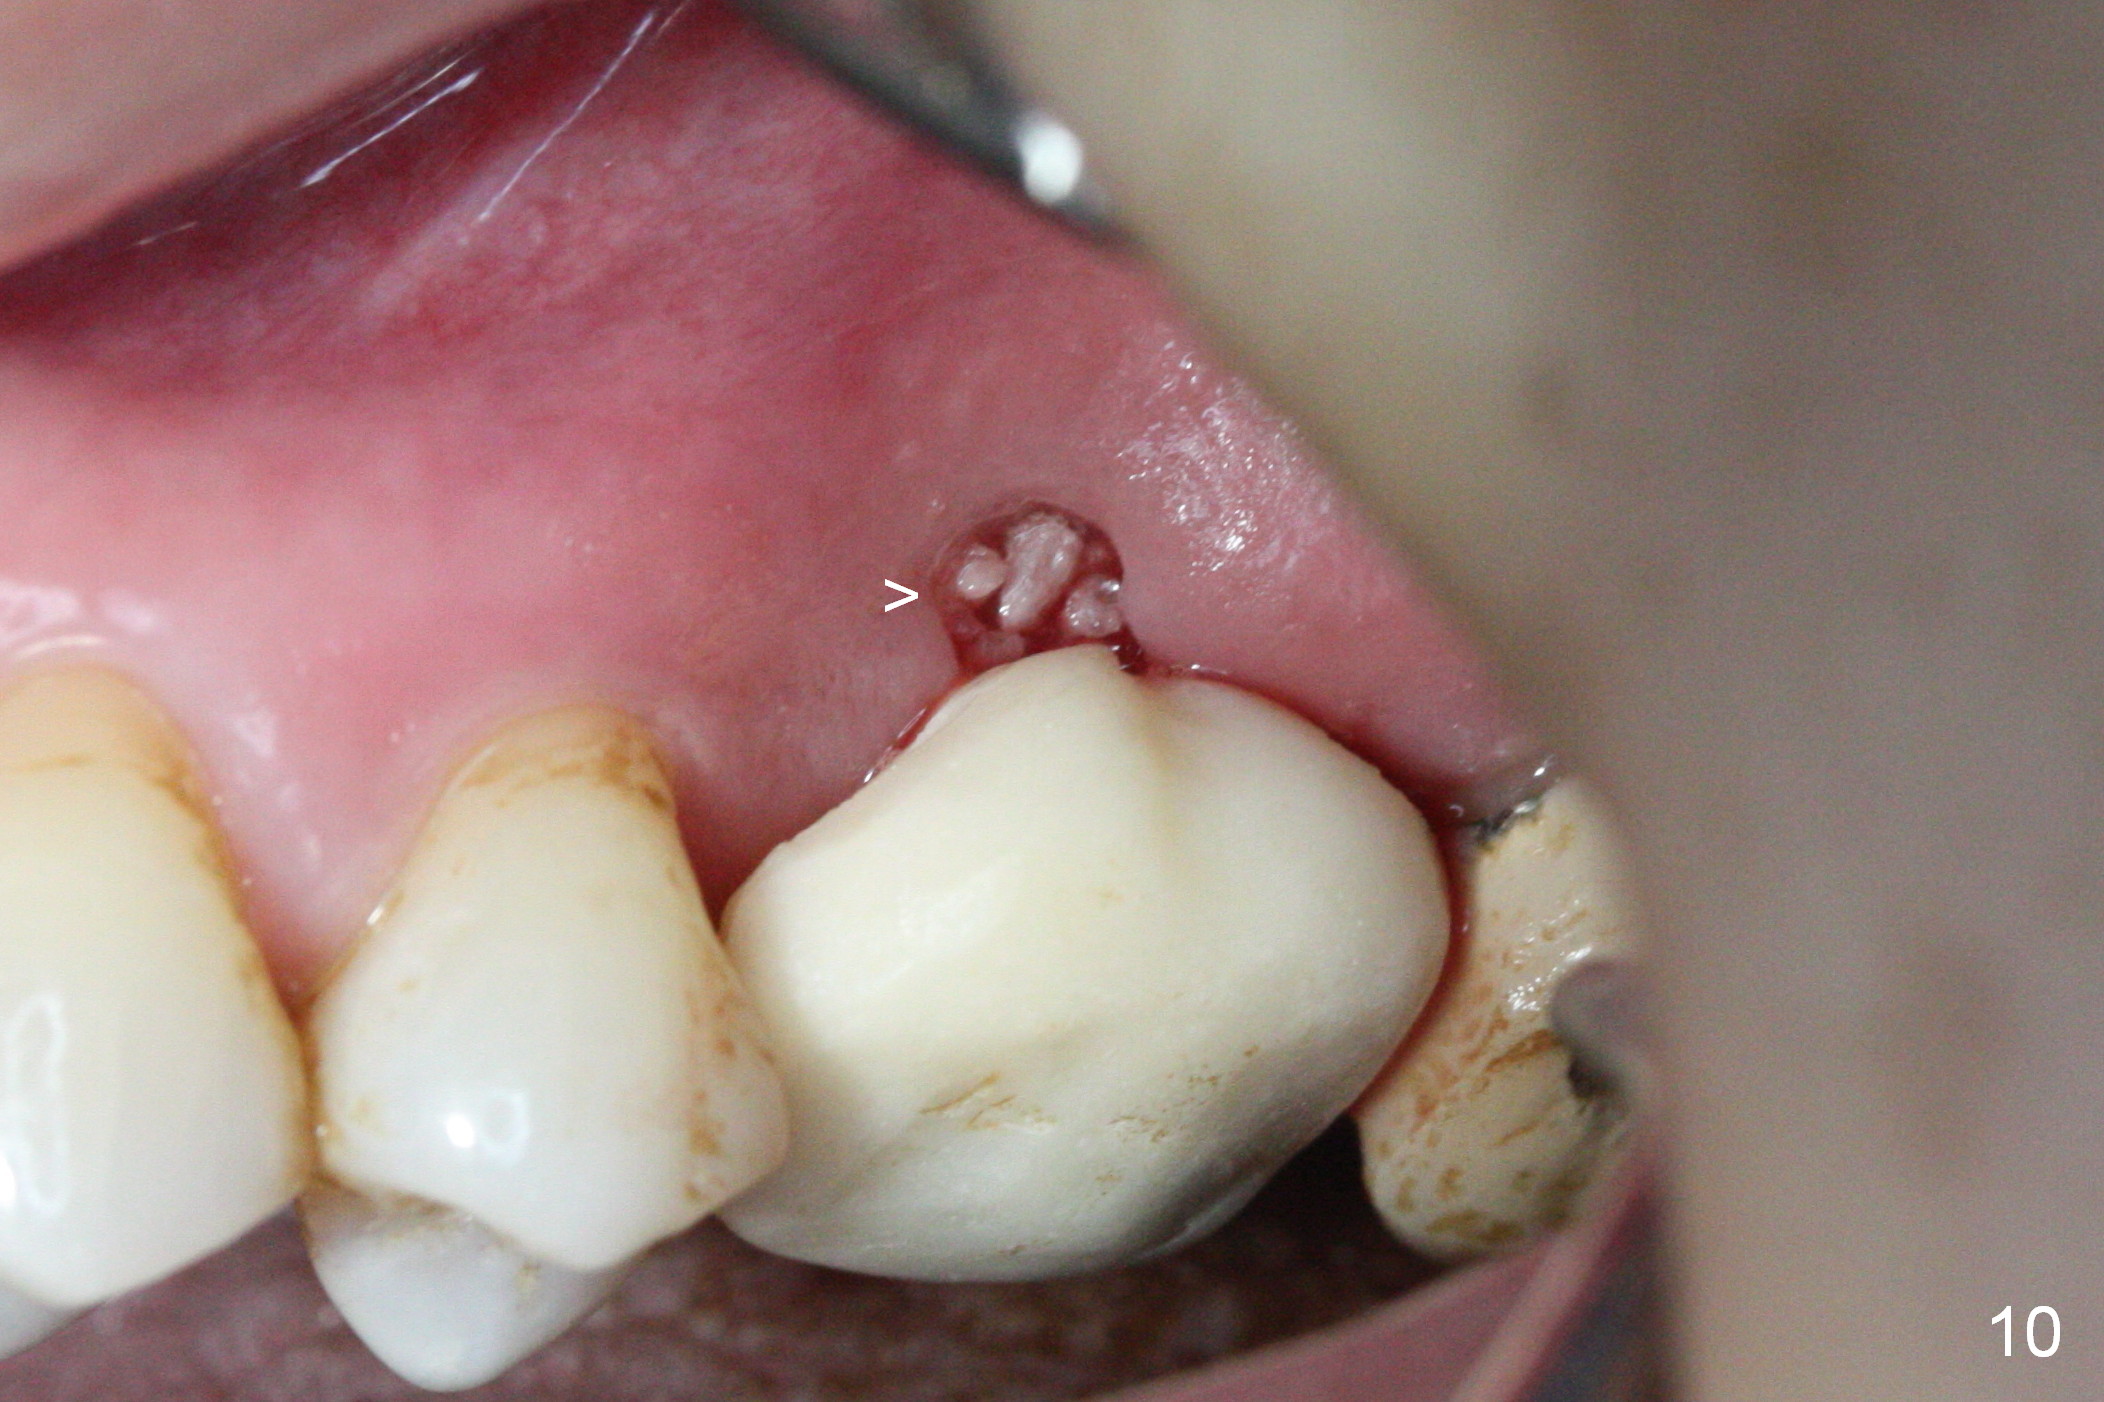

There is abundant subgingival calculus on the surfaces of the extracted tooth at #14 (Fig.1: P: palatal; MB: mesiobuccal), corresponding to the large empty socket (Fig.2 without septal bone, the buccal plate being low). Osteotomy is established palatally with Magic Expander (ME) 3.0 mm for ~ 3 mm deep (Fig.3,4) with minimal stability so that it moves during X-ray taking (Fig.4). Since the bone is dense, Magic drill 4.3 mm is used after application of ME 3.8 and 4.3 mm to complete sinus lift (Fig.5 (panoramic X-ray)). A 5x11 mm implant is placed with ~ 30 Ncm, followed by insertion of 6.5x4(3) mm Hexa abutment, bone graft and collagen membrane (Fig.6). The latter is kept in placed with an immediate provisional with clearance from the opposing dentition (Fig.7 *). Between the 1st and 3rd weeks postop, the buccal gingiva recedes with loss of bone graft (Fig.8 <) and implant thread exposure (Fig.9 * (A: abutment)). After inducing hemorrhage, allograft is placed (Fig.10 >), followed by collagen dressing (Fig.11 >). The wound closes by adding new acrylic (Fig.12 *). Thirteen days later, food is trapped in the buccal gap (Fig.13 ^). It appears that the provisional does not help wound healing. The provisional and abutment are removed; incorporating bone graft (Fig.14 *) and the implant are exposed. After placing collagen plug against the bone graft and implant, the wound is closed by periodontal dressing.